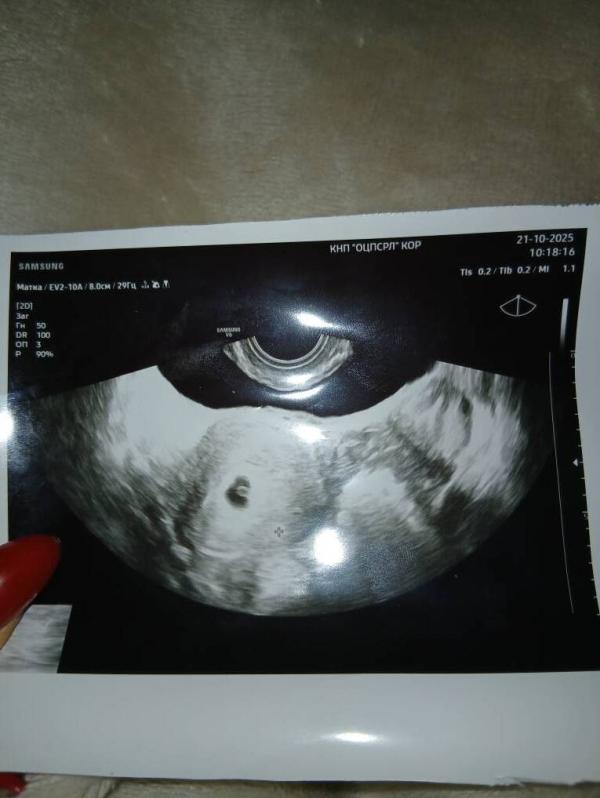

Инстамама ❤·Мама дочки (5 лет), беременна (7 нед.)

Первое УЗИ на 6 неделе беременности: фото малыша

6 недель 🥰 первая фоточка

21.10.2025